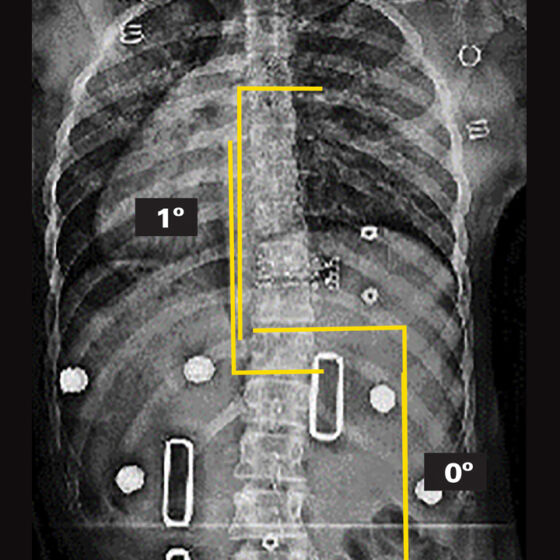

26° Right Thoracic, 26° Left Thoracolumbar Curve

25° Right Thoracic, 21° Left Lumbar Curve

45° Right Thoracic Curve

34° Right Thoracic, 30° Left Lumbar Curve